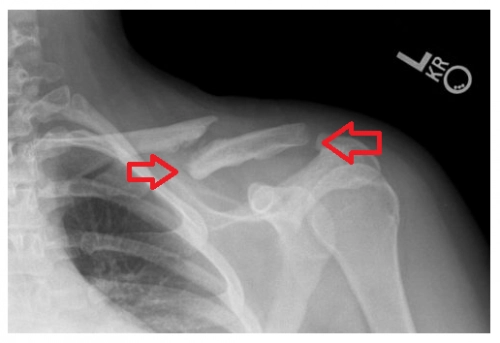

Trường hợp xương đòn bị gãy làm đôi và chệch khỏi vị trí ban đầu thì cần phẫu thuật

- Đoạn gãy trồi lên cao và nhô lên dưới da do các cơ kéo lên. Vì xương đòn nằm ngay dưới da, nếu mổ thì khó lành hơn là để yên, về mặt thẩm mỹ thì sẽ để lại vết sẹo to, dài trên vai rất xấu.

- Xương đòn chọc ra da, mảnh xương gãy chọc vào đỉnh phổi gây biến chứng ở phổi, gãy hai xương đòn (vì sợ ảnh hưởng đến hô hấp do bệnh nhân thở sẽ bị đau)

- Gãy xương đòn di lệch quá nhiều so với vị trí ban đầu

Hoặc khi xương đòn chồi lên khỏi bề mặt da